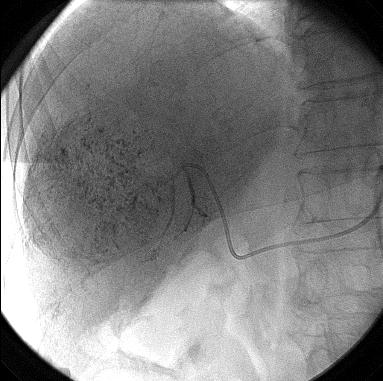

(九)、肝动脉栓塞化疗术

消化内科开展各种良性及恶性疾病的介入治疗肝动脉栓塞化疗及其它肿瘤栓塞化疗术(TAE)、布-加氏综合征扩张及支架置入术等。